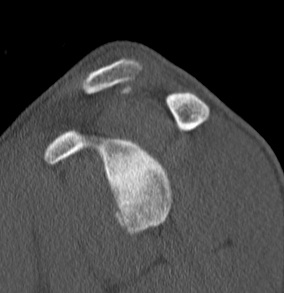

CT scan

Hill Sachs

Hill Sachs 3D CT

Anterior glenoid bony deficiency - inverted pear appearance